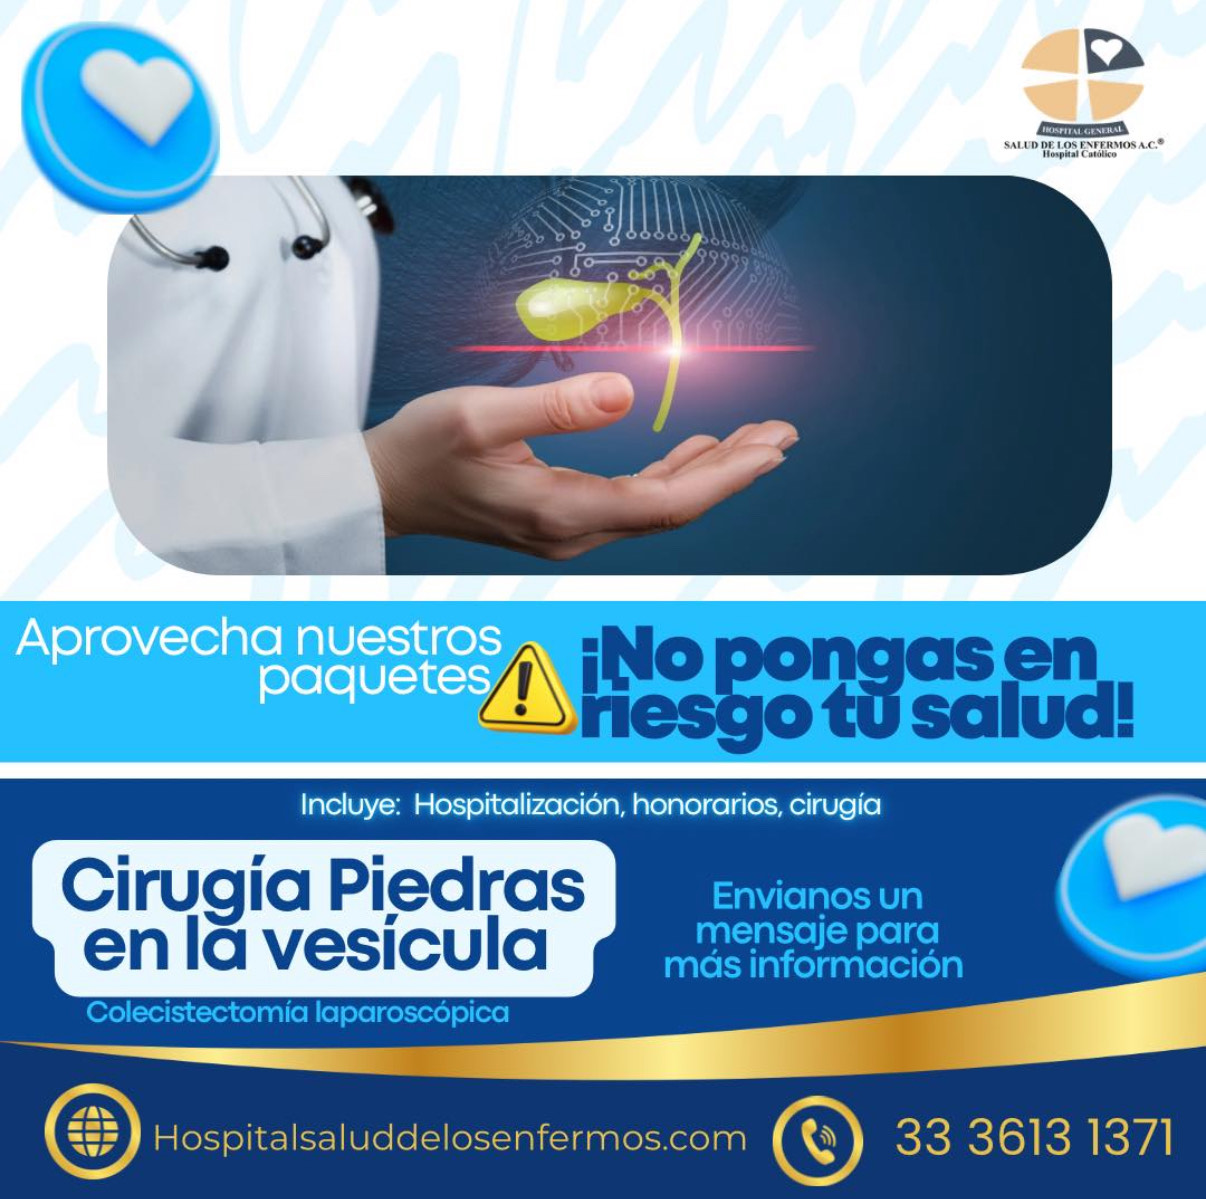

Cirugía Piedras en la Vesícula

Las piedras en la vesícula pueden causar dolor y complicaciones si no se tratan a tiempo. En el Hospital Salud de los Enfermos realizamos cirugía laparoscópica segura y mínimamente invasiva.

Inclue: hospitalización, honorarios y cirugía.

Recuperación rápida y menor dolor postoperatorio.